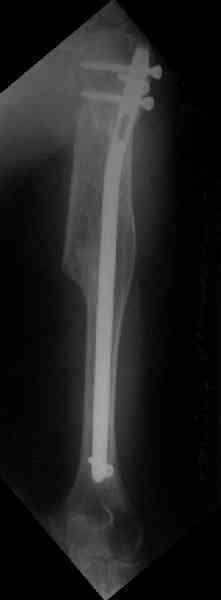

Здесь нет необходимости в серкляже. Вмешиваться на промежуточных

отломках приходится, если есть угроза перфорации кожи, или

промежуточный отломок попал в фасцию, как пуговица в петлю. В

приложении сегментарный оскольчатый перелом плеча в проксимальном

отделе, фиксированный больщеберцовым стержнем. Как видите, обошлось

без серкляжа. Функция полная.